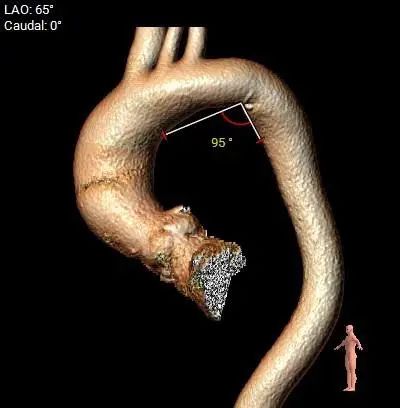

主动脉瓣环水平夹角47度,非横位心,主动脉弓宽度、角度可,弓部存在少量散在钙化。

虚拟瓣环与水平夹角